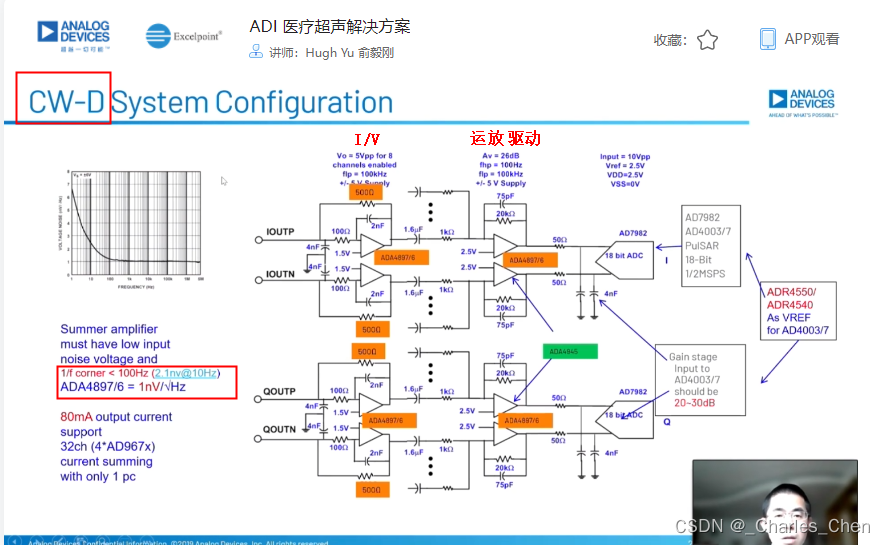

连续波多普勒(CWD)

多数的心脏检查和一些通用的超声成像系统中,常常使用连续波多普勒CWD以确保精确测量心脏内高速流动的血液。CWD模式下,超声传感器单元以传感器孔径为中心分割成对等的两部分。一半单元用于发射,产生CWD聚焦波束;另一半单元用于接收,产生聚焦的接收波束。发射单元的驱动波形为多普勒频率的方波,频率范围通常为1MHz至7.5MHz。发射波形的抖动必须足够小,以防止相位噪声对多普勒频移检测的影响。通过正确调整发射波形的相位,实现发射波束聚焦。类似地,通过正确调整接收波形的相位并进行叠加,实现CWD接收信号聚焦。在此模式下,发射和接收同时进行,有用的多普勒信号频率和不移动的人体组织在发射基波频率下产生的强反射信号的频率相差只有几kHz。处理如此大的信号所需要的动态范围已经超出了图像接收通道VGA、AAF和12位ADC可以承受的范围。因此,CWD必须使用其它高动态范围接收解决方案。

CWD接收机通常使用两种方法处理CWD信号。第一种方法是高性能超声系统在LNA输出端提取接收到的CWD信号。本振频率等于发送频率的混频器对信号进行波束成形,再混频至基带进行处理。I/Q本振信号可以逐通道调整相位,对接收到的CWD信号相位进行偏移。混频器输出相叠加,经带通滤波器,最后进入ADC进行采样。采样得到的基带波束信号处于音频范围(100Hz至50kHz),采用工作在音频频率范围的ADC对I和Q CWD信号进行数字化。这些ADC需要出色的动态范围,以便处理运动组织产生的较大的低频多普勒信号和血液产生的微弱信号。

另一种方法是使用延迟线接收CWD信号,该方法常用于低成本设备。在此方法中,信号还是从LNA输出提取,然后转化成电流信号。通过一个交叉开关对相同相位的通道进行叠加,产生8至16路独立输出,具体由接收波束成形器决定。延迟线产生延迟,并将这些信号求和构成一路波束成形RF信号,然后利用一个本振频率等于发送频率的I/Q混频器将信号混频至基带,然后将基带音频信号滤波后,转换至数字形式。